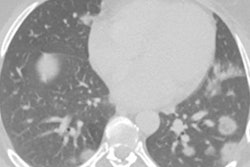

SARS-CoV-2, the virus that causes COVID-19, primarily attacks the lungs but has also been associated with eye conditions such as conjunctivitis and retinopathy, the authors noted. Although eye abnormalities in COVID-19 patients have been documented on MRI, research on the characteristics and frequency of these eye complications is limited.

This study, conducted under the auspices of the French Society of Neuroradiology (SFNR), included 129 patients with severe COVID-19 confirmed by reverse transcription polymerase chain reaction (RT-PCR) who underwent brain MRI scans for a variety of reasons (delayed awakening despite the discontinuation of sedation, 67%; agitation and confusion after awakening, 22%; and agitation and hallucinations, 11%). Patients were treated at 16 hospitals between March and May 2020.